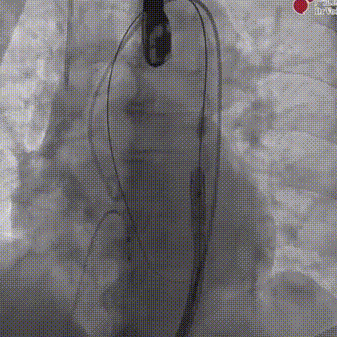

造影下瓣膜定位后,180bp快速起搏下+1cc释放20mm SAPIEN 3瓣膜主动脉;

造影下瓣膜定位

快速起搏下+1cc释放20mm瓣膜